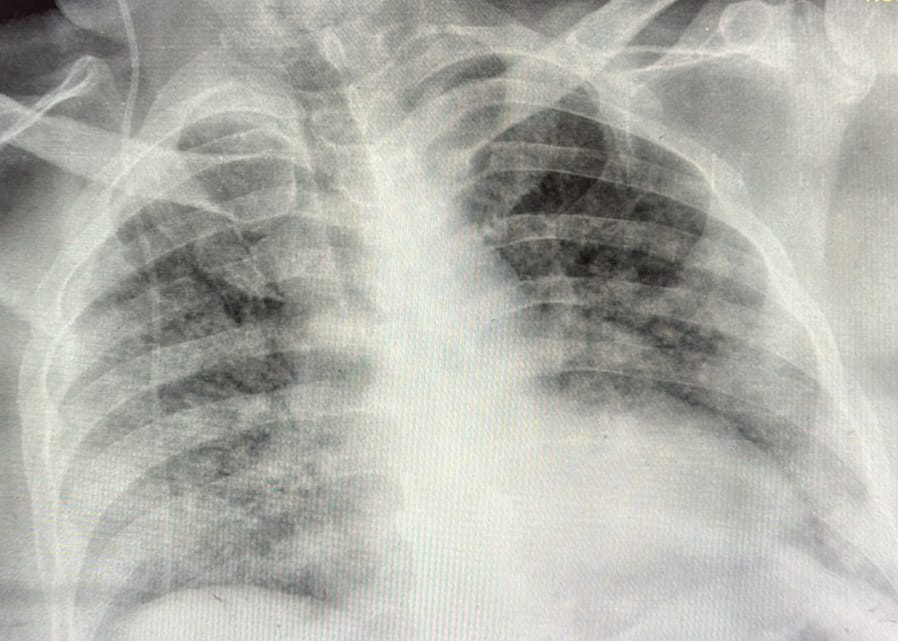

draurtecho Feb 12, 2025 tuberculosis miliar o diseminada La tuberculosis diseminada, puede dar síntomas inespecíficos, como agotamiento, pérdida de peso, tos seca, y en algunas ocasiones fiebre de predominio por la tarde. El órgano que más comúnmente se afecta son los pulmones. En la tomografía de tórax se puede visualizar como nódulos. A continuación como se puede observar la tuberculosis diseminada en una TAC de tórax. No Comments InNeumología